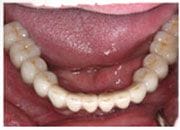

治療後